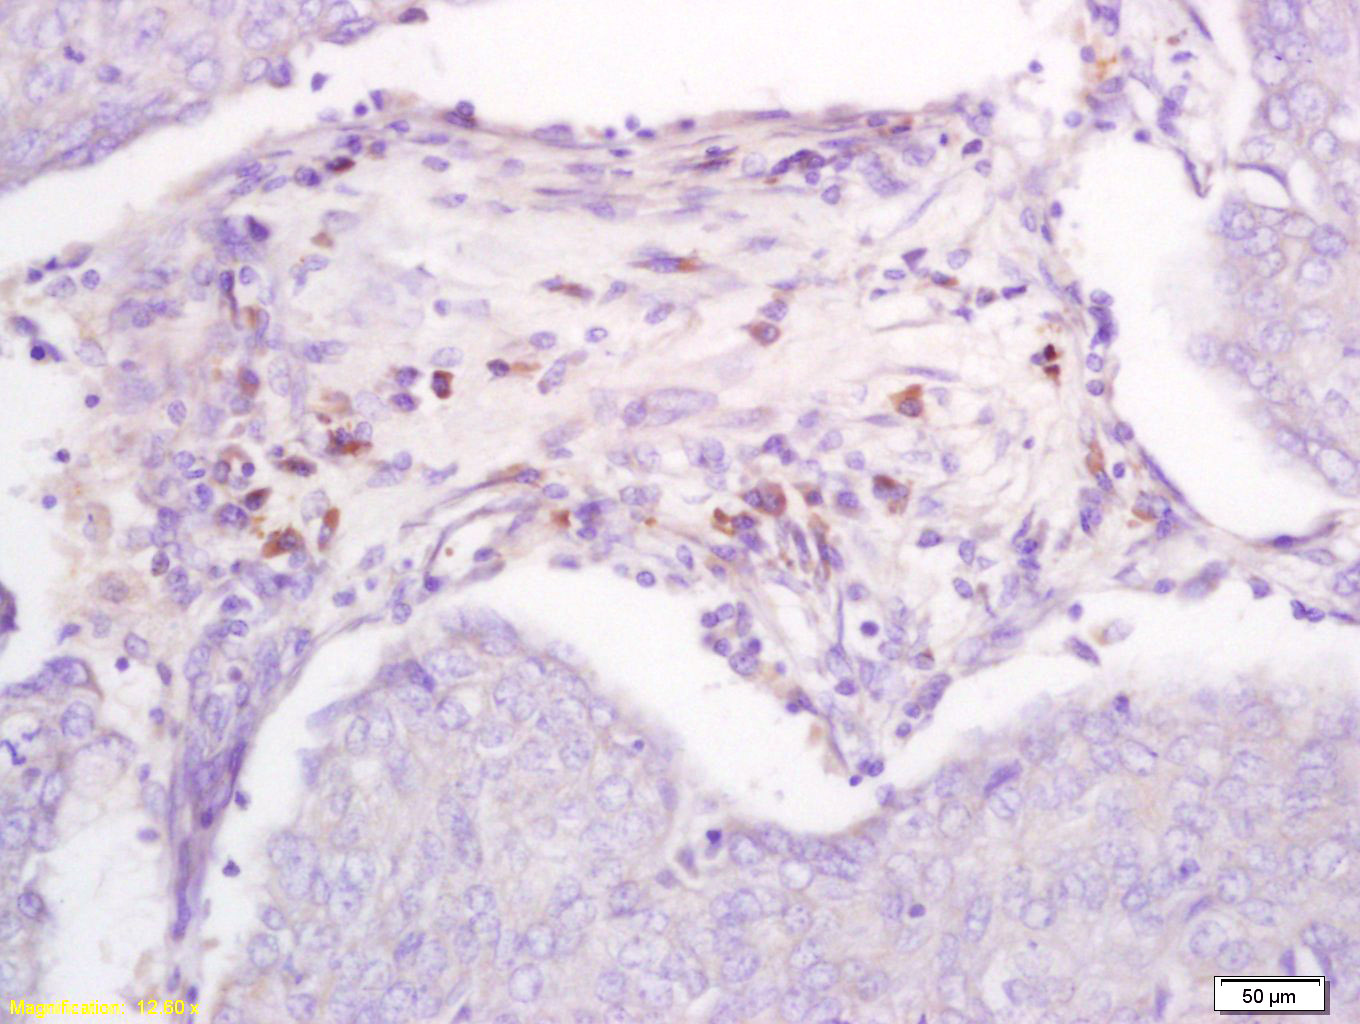

Antigen retrieval: citrate buffer ( 0.01M, pH 6.0 ), Boiling bathing for 15min; Block endogenous peroxidase by 3% Hydrogen peroxide for 30min; Blocking buffer (normal goat serum,C-0005) at 37℃ for 20 min;

Incubation: Anti-DBC2 Polyclonal Antibody, Unconjugated(bs-4274R) 1:200, overnight at 4°C, followed by conjugation to the secondary antibody(SP-0023) and DAB(C-0010) staining